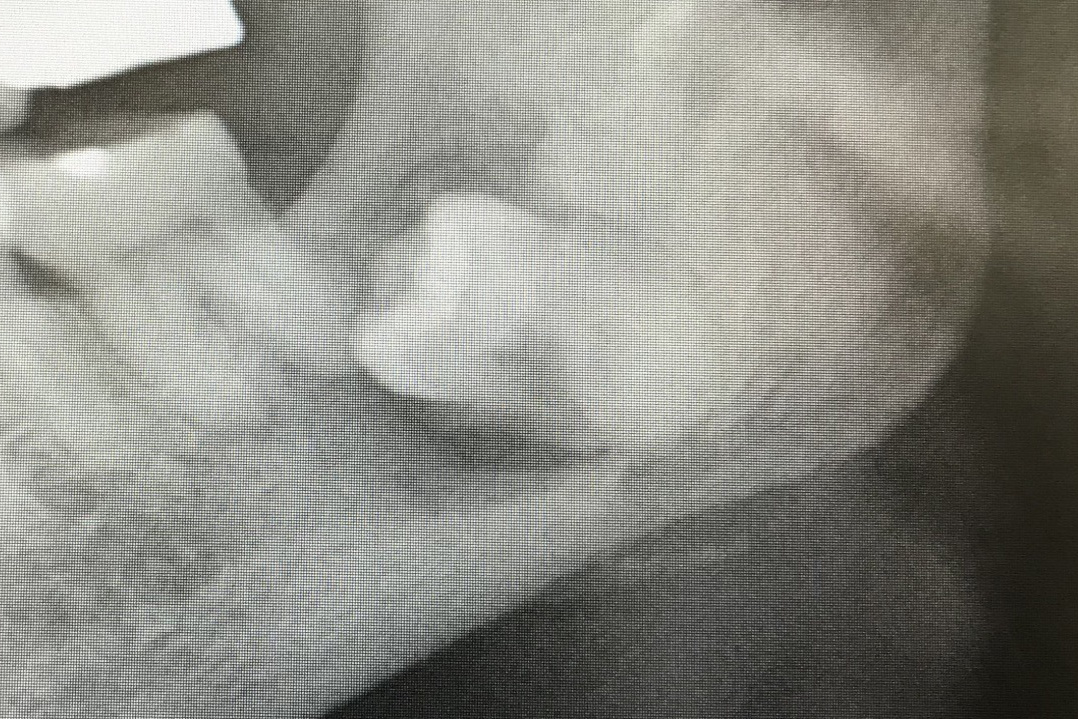

☆☆☆

神経と親知らずが非常に近く,抜歯をすると麻痺が出る可能性が非常に高そうです.二回に分けて親知らずを抜くことにしました.

まず,歯の頭の部分を分割します.神経に非常に近いので分割も細心の注意を払って行います.

歯の頭だけを除去しました.そのスペースに根っこが移動してくるのを半年ほど待ちます.これももちろん保険適応です.自費のところもあるみたいです.